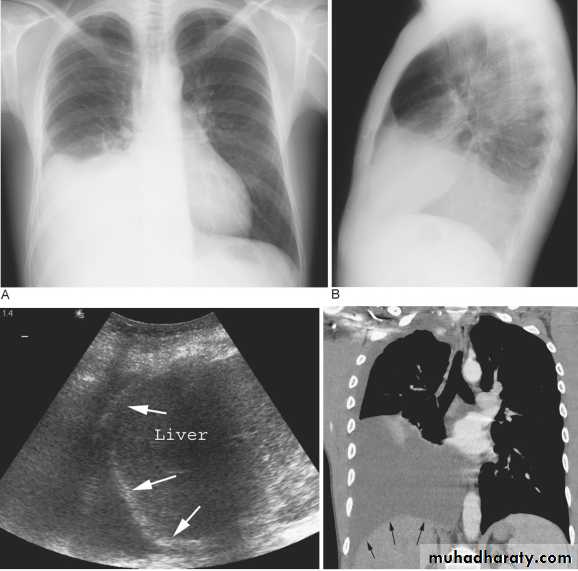

Subpulmonary pleural effusion. On the (A) erect PA and (B) lateral radiograph the effusion simulates a high hemidiaphragm. (C) Ultrasound and (D) CT clearly show that the effusion is located above the diaphragm. Arrows = diaphragmatic area.